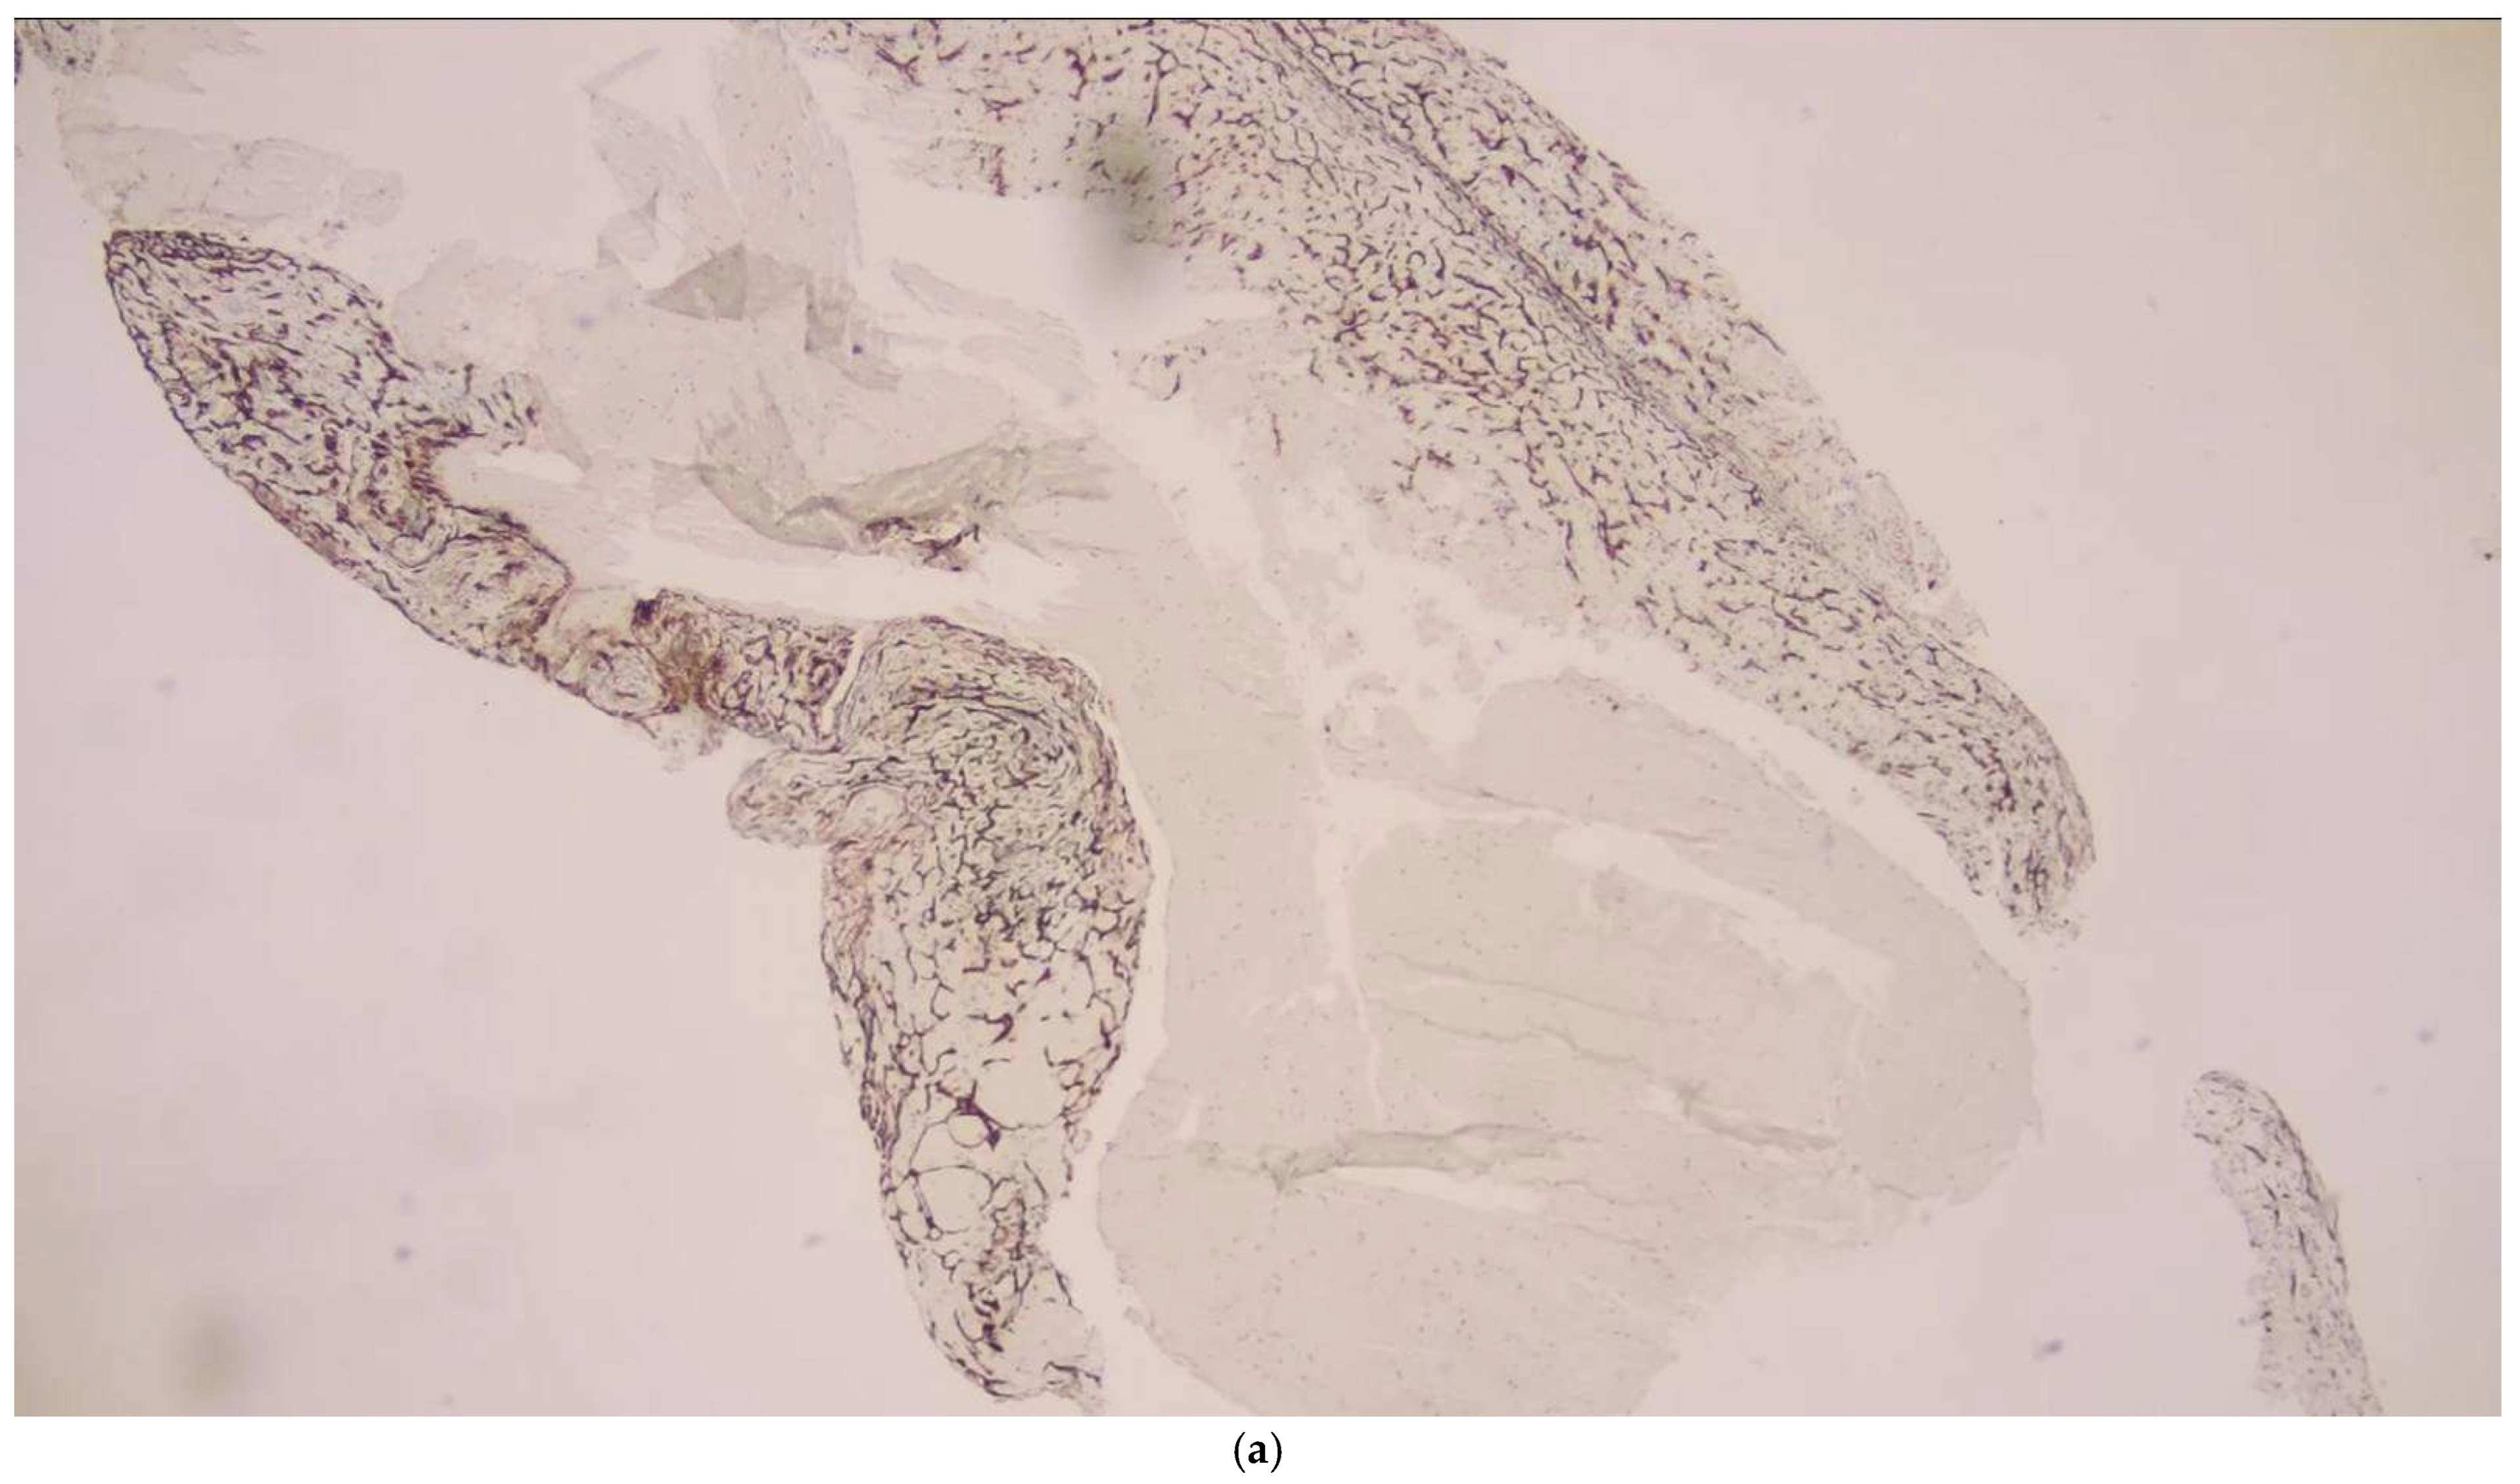

2.6. Histopathological Examination

- Schuhmann, M.K.; Gunreben, I.; Kleinschnitz, C.; Kraft, P. Immunohistochemical Analysis of Cerebral Thrombi Retrieved by Mechanical Thrombectomy from Patients with Acute Ischemic Stroke. Int. J. Mol. Sci. 2016, 17, 298. [Google Scholar] [CrossRef]

- Pusztaszeri, M.P.; Seelentag, W.; Bosman, F.T. Immunohistochemical expression of endothelial markers CD31, CD34, von Willebrand factor, and Fli-1 in normal human tissues. J. Histochem. Cytochem. 2006, 54, 385–395. [Google Scholar] [CrossRef]

- Müller, A.M.; Hermanns, M.I.; Skrzynski, C.; Nesslinger, M.; Müller, K.M.; Kirkpatrick, C.J. Expression of the endothelial markers PECAM-1, vWf, and CD34 in vivo and in vitro. Exp. Mol. Pathol. 2002, 72, 221–229. [Google Scholar] [CrossRef]